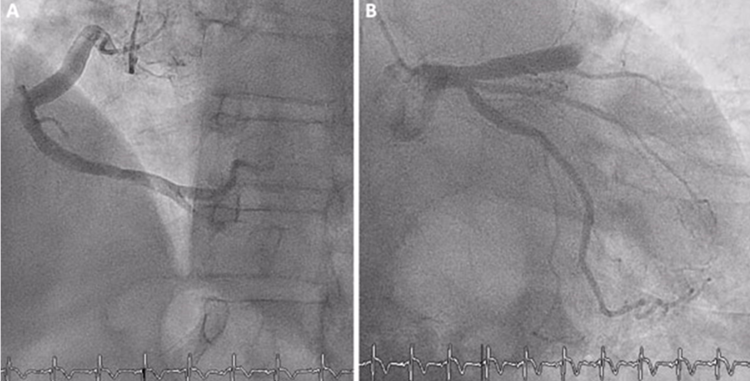

• Coronary angio documented diffuse coronary ectasia with thrombotic occlusion of the mid-right coronary artery.

• The patient was a 53-year-old male with a history of type 2 diabetes mellitus, obesity, and smoking, who was admitted to our hospital with an inferior STEMI. Coronary angiography revealed a thrombotic occlusion of the mid segment of the right coronary artery, with a high thrombus burden (Figure 1, Video 1 in the supplementary material).

The subject is a 53-year-old male with a medical history encompassing type 2 diabetes mellitus, obesity, and a smoking habit. He was admitted to our hospital following an episode of lower STEMI. Coronary angiography revealed a thrombotic occlusion in the mid-segment of the right coronary artery, characterized by a notably high thrombotic load.